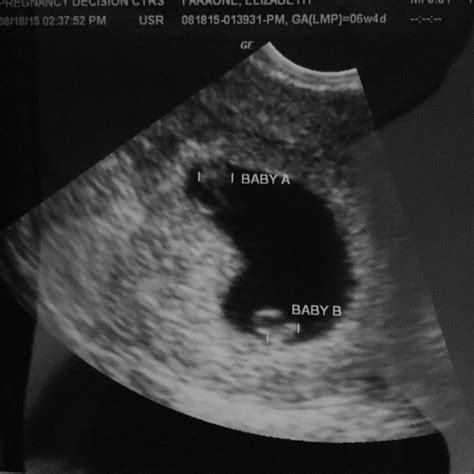

A 6 week sonogram twins is typically the first ultrasound performed during a twin pregnancy. At this stage, the embryos are still very small, but the ultrasound can detect the presence of two gestational sacs, which are the early structures that will develop into the amniotic sacs. This confirmation is essential for early detection and monitoring of twin pregnancies.

• Detection of Gestational Sacs: The primary goal of the 6 week sonogram twins is to detect the presence of two gestational sacs. Each sac contains an embryo and will eventually develop into an amniotic sac.

• Presence of Gestational Sacs: The detection of two gestational sacs confirms a twin pregnancy. This is a crucial finding that sets the stage for ongoing monitoring and care.

• What if only one gestational sac is detected? If only one gestational sac is detected, it may indicate a single pregnancy or a vanishing twin, where one embryo did not develop. Further monitoring will be necessary to confirm the status of the pregnancy.